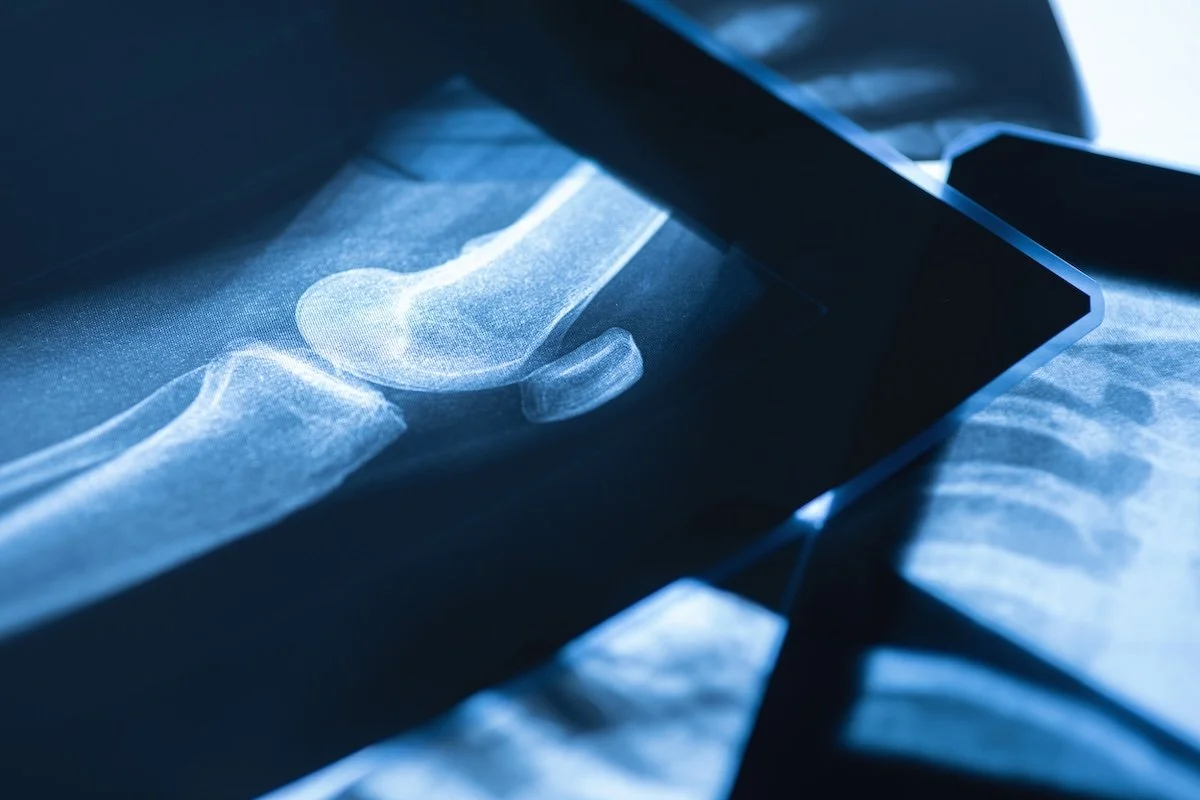

A bone density test (DEXA scan) is a quick, painless imaging study that measures the strength and mineral content of your bones—most often in the spine and hips. It uses very low radiation and is the gold standard for diagnosing osteoporosis, detecting early bone loss, and assessing fracture risk. The results guide personalized recommendations for nutrition, lifestyle changes, and medical treatment to protect long-term bone health.